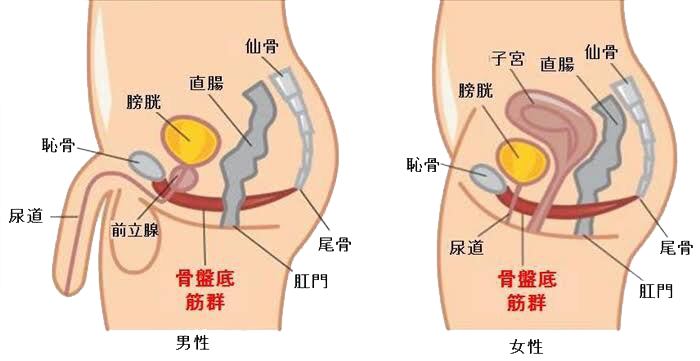

骨盤底筋群とは?

骨盤底筋群(こつばんていきんぐん)とは、骨盤の底にあるハンモック状の筋肉の集合体で、複数の筋肉や腱でできています。恥骨や坐骨、尾骨などの骨を支えてます。

内臓を支える

骨盤底筋は、膀胱や直腸、子宮といった内臓を、下から支える重要な役割を持っています。

骨盤底筋がゆるんでしまうと、内臓を正しい位置に保持できなくなり、さまざまな健康問題を引き起こすことがあります。

排泄をコントロールする

骨盤底筋を構成する筋肉には、便や排尿と関係のある筋肉が含まれています。骨盤底筋のゆるみとは、これらの筋肉がゆるんでしまうこと。そのため、排泄トラブルへとつながることがあります。